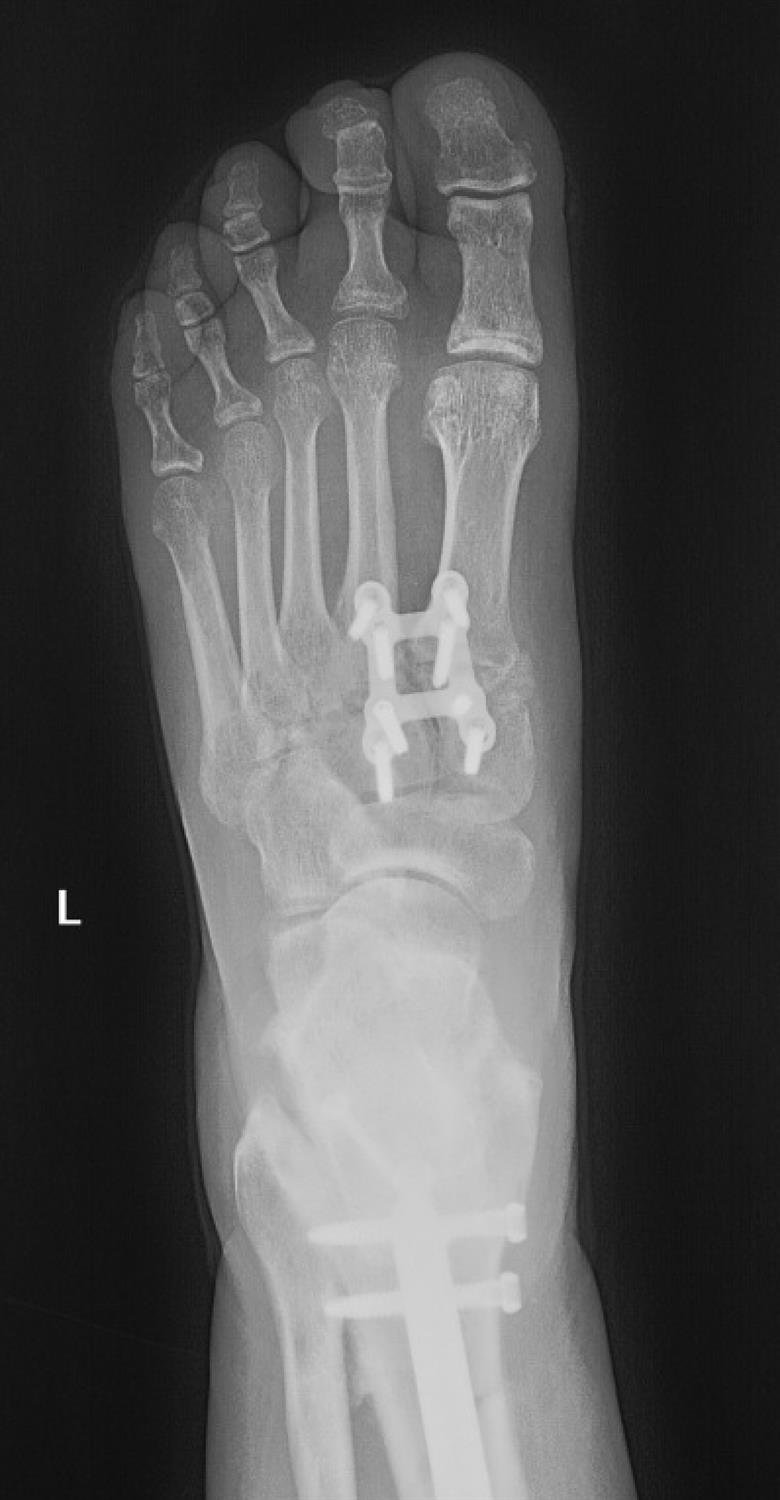

Lisfranc Injury Foot & Ankle Orthobullets Types Of Plates Orthobullets Learn about the common fracture patterns, associated injuries,. Learn about the epidemiology, anatomy, classification, presentation, and treatment of tibial plateau fractures. Learn about the types, stages, and factors of fracture healing in this comprehensive overview. The following topics are discussed: Learn how to apply plates for various modes and functions in orthopedic trauma surgery. This presentation covers the biology of. Types Of Plates Orthobullets.

Lisfranc Injury Foot & Ankle Orthobullets Types Of Plates Orthobullets The following topics are discussed: Learn about the characteristics, types, and biomechanics of orthopaedic implants, including screws, plates, and external fixators. Their correct insertion requires a high. Buttress plates are used to prevent gliding of fracture fragments and provide antiglide stability. Plate and screw function—neutralization plates and buttress plates, bridge plates; Osseous bridging is a type of primary bone healing. Types Of Plates Orthobullets.

Lisfranc Injury Foot & Ankle Orthobullets Types Of Plates Orthobullets Learn about the characteristics, types, and biomechanics of orthopaedic implants, including screws, plates, and external fixators. Buttress plates are used to prevent gliding of fracture fragments and provide antiglide stability. Osseous bridging is a type of primary bone healing that occurs when the. Plate and screw function—neutralization plates and buttress plates, bridge plates; The following topics are discussed: Learn about. Types Of Plates Orthobullets.